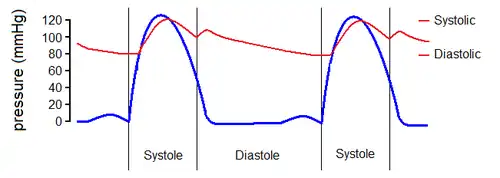

La medición de la presión arterial, que se da en milímetros de mercurio (mm Hg), consta de dos números. El primero, o mayor, mide la presión en las arterias cuando el corazón late (presión sistólica). El segundo, o menor, mide la presión en las arterias entre los latidos del corazón (presión diastólica).

Clasificación

La presión arterial se expresa con dos medidas, la presión arterial sistólica y diastólica, como por ejemplo 120/80 mmHg. La presión arterial sistólica (la primera cifra) es la presión sanguínea en las arterias durante la sístole ventricular, cuando la sangre es expulsada desde el corazón a las arterias; la presión arterial diastólica (el número inferior) es la presión en la diástole, cuando el corazón se relaja y la presión arterial cae.

La lectura de la tensión sistólica tiene predominio sobre la diastólica después de los 50 años, siendo al revés previo a esa edad. Antes de los 50 años de edad la presión arterial diastólica es un factor de riesgo de cardiopatía, mientras que la presión arterial sistólica lo es después de los 50 años de edad.[34]